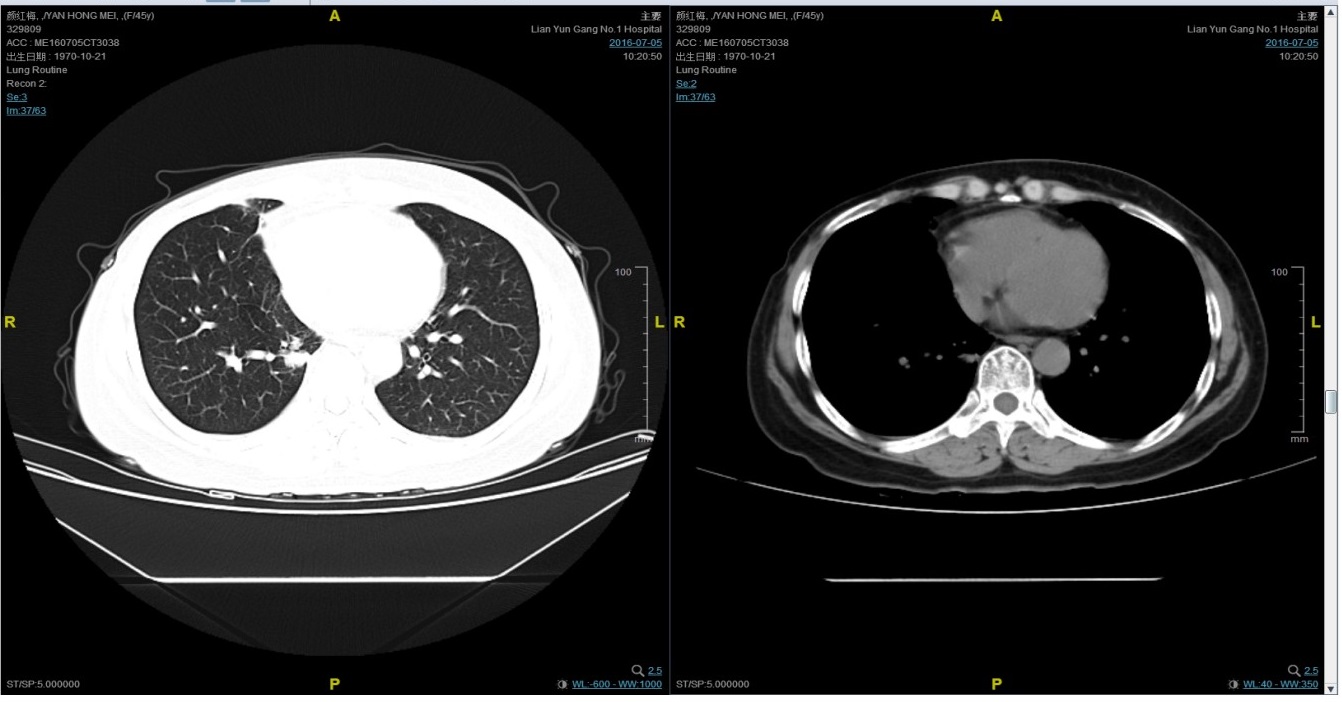

2016-7-5化疗结束后复查CT,疗效评价稳定。

后续治疗

患者继续曲妥珠单抗维持治疗,且自服中药。